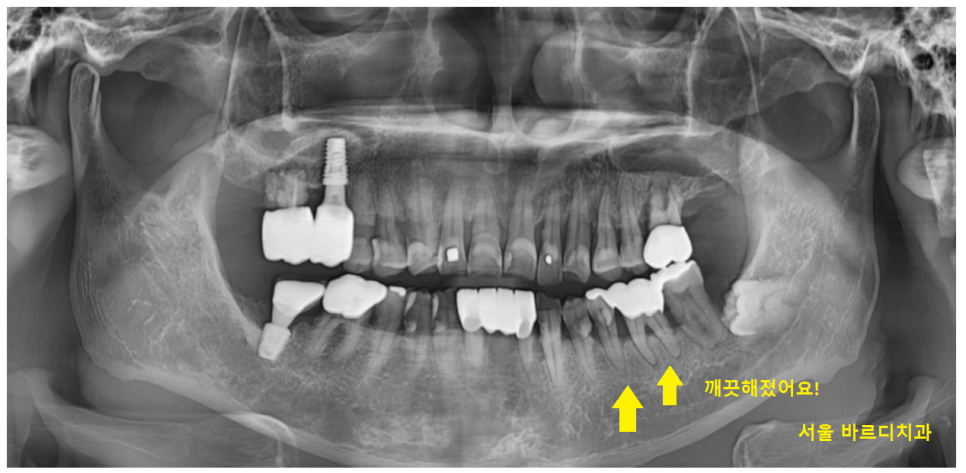

치료 후 사진을 보시면

깨끗해 진게 보이시죠~?

23.11.18

잇몸 뿌리에 붙어있던 오돌토톨한게

다 사라졌습니다.

이제 상일동역 스케일링을 6개월마다 받으시면서

계속 관리해주시면

잇몸치료 자주 받을 필요 없답니다!

오늘은 상일동역 스케일링 다음과정인

잇몸치료를 받고 효과를 보신 환자분을 소개해드렸습니다.